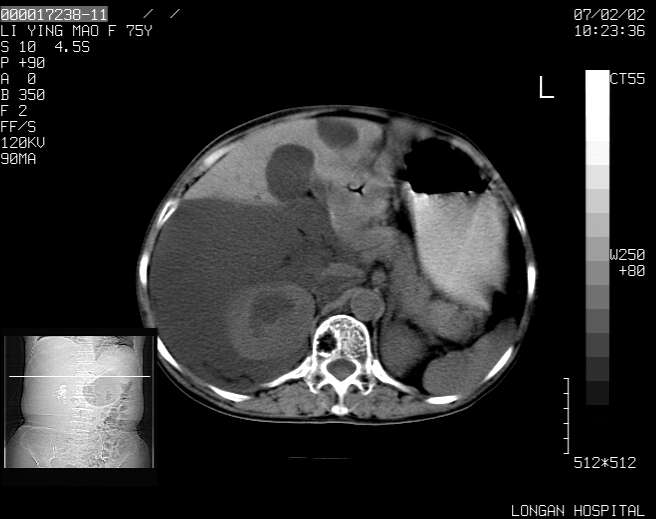

以下是引用dyqct在2007-2-10 8:53:00的发言:[br]考虑:1、肝脏多发囊肿[br] 2、左肾囊肿,右肾多发结石并积水。[br] 3、右胸少量积液。[br] 4、右肾周包裹性积液或淋巴管瘤(有见缝就钻的征象、薄隔、小结节状钙化)?[br] 5、腰椎动脉瘤样骨囊肿?[br] [br] [br]